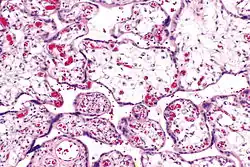

| Micrograph of villous immaturity. H&E stain. | |

Placental villous immaturity is chorionic villous development that is inappropriate for the gestational age.

Immature chorionic villi are larger and have more central blood vessels; thus, the diffusion distance for gas and nutrient exchange is larger and, therefore, placental function is impaired.